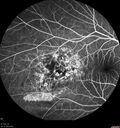

64 year old man. Diagnosed with hemangioma in 2015. PDT in 2016. Images are from 2020 when fluid started to reaccumulate. Needed PDT repeated two more times. PDT treatments: [1] 2/19/2015 -  Pavan (IOP  problem after PDT)  AND [2] 11/2/21 PDT (7 mm temporal to fovea) - SMC  AND [3] 7/22/22 PDT 7.5 mm Temporal to the fovea

Choroidal Hemangioma Requiring PDT repeatedly217 views64 year old man. Diagnosed with hemangioma in 2015. PDT in 2016. Images are from 2020 when fluid started to reaccumulate. Needed PDT repeated two more times.

PDT treatments: [1] 2/19/2015 -  Pavan (IOP  problem after PDT)  AND [2] 11/2/21 PDT (7 mm temporal to fovea) - SMC  AND [3] 7/22/22 PDT 7.5 mm Temporal to the fovea